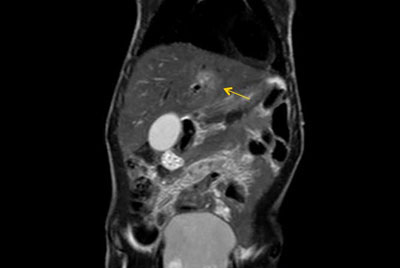

Pancreas nodule – Free breathing